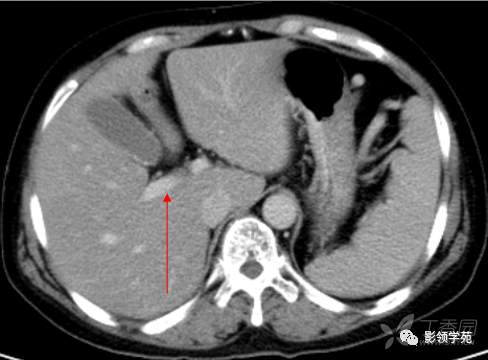

胆囊窝层面CT横断面解剖

CT:首先找出肝脏的三大静脉:肝中静脉,肝左静脉,肝右静脉,找出门静脉及其分叉部位。门静脉分叉部位可以区分上段和下段,即肝S8/S5,S7/S6,门静脉分叉以上为S8、S7;肝右静脉和肝中静脉之间是右前叶,肝右静脉以后是右后叶

一般规律,从CT上看,最先看到的是S8然后是S2、3,肝左外叶以肝裂为界,左内叶为肝裂和肝中静脉之间的区域,胆囊往下的层次是S5,最后的层面一般是S6,下腔静脉和门静脉夹着的是尾状叶,即S1。